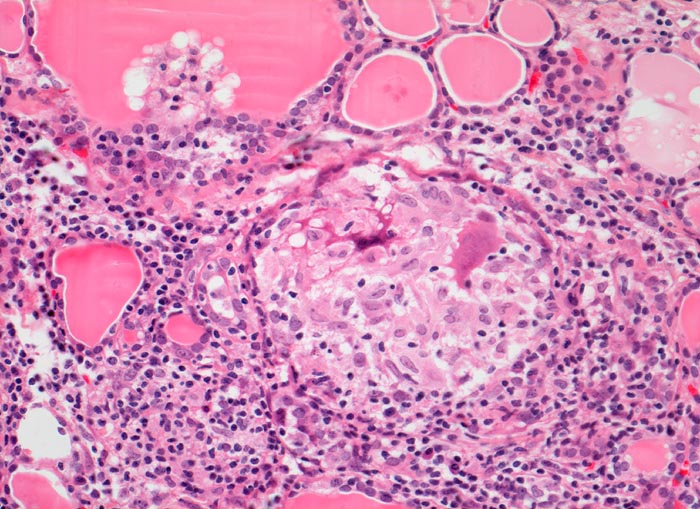

AP/ Subakute Thyeroiditis de Quervain

Subakute Thyeroiditis de Quervain

Schilddrüse

Normalbefund